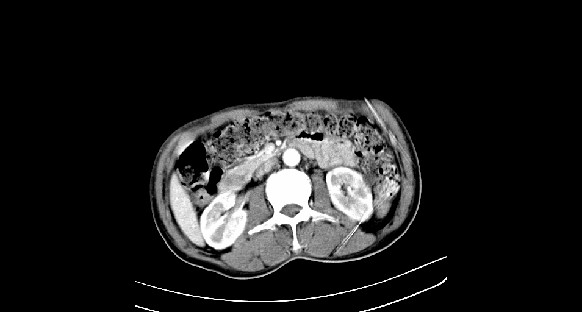

男性,70岁,体检b超发现左肾占位,请各位战友发表一下观点

左肾有两个病灶,且较大的病灶内可见点状钙化灶,增强扫描边缘也是呈渐进性强化,中央部分未见明显强化